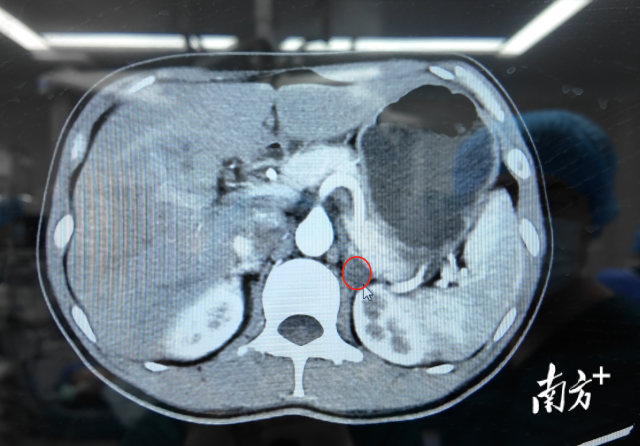

隨後,增強CT檢查揭開了答案:林辰辰的左側腎上腺上長了一個1.8cm的結節。“這個情況屬於泌尿外科的診療範疇,建議你轉到專科進一步檢查和治療。”蘇海明的建議,為林辰辰的治療指明了新的方向。

增強CT影像檢查結果顯示,林辰辰的左側腎上腺上長了一個 1.8cm 的結節